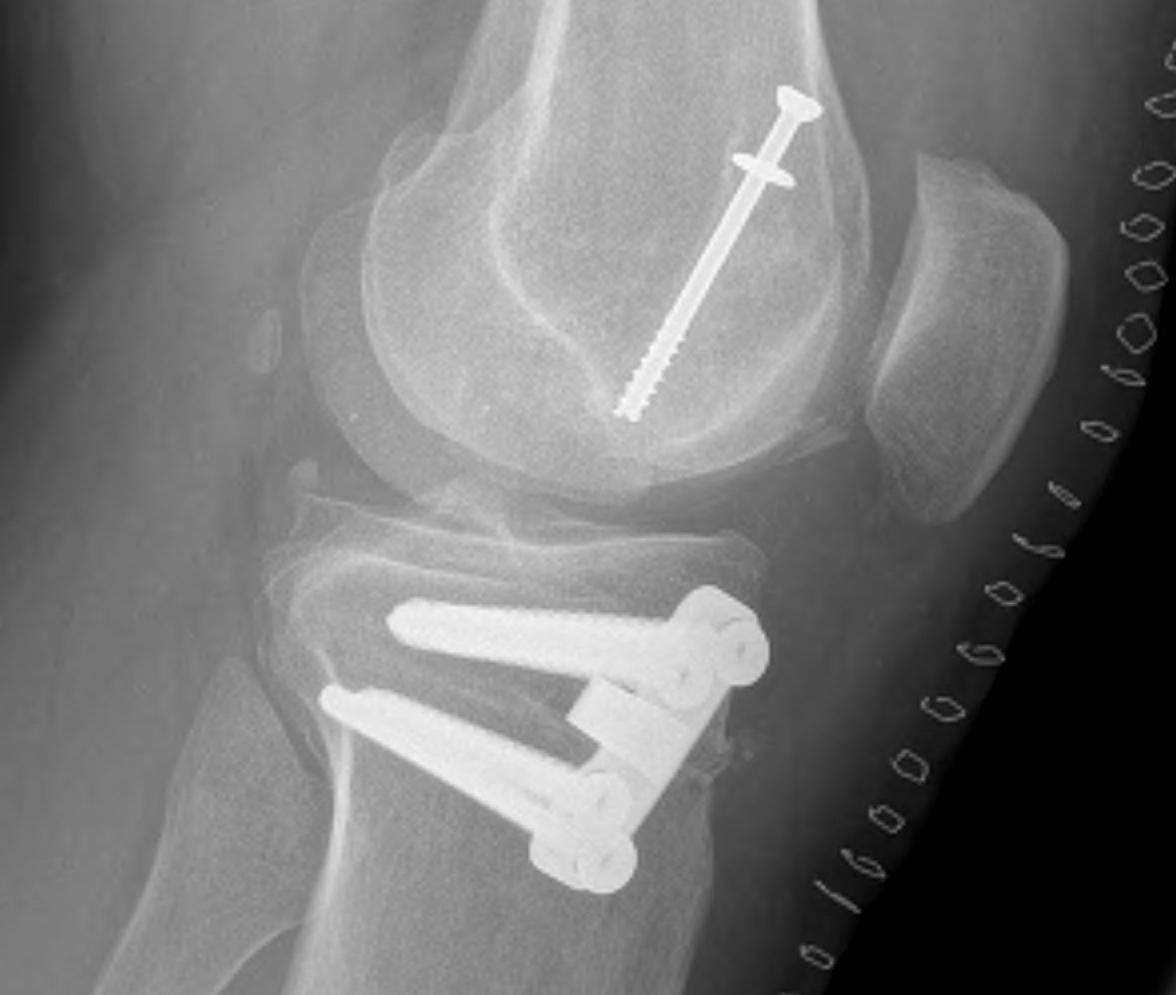

• Cartilage defects

• Background

• Management